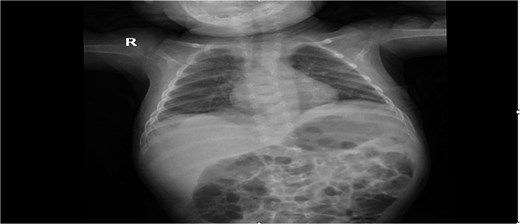

Chest radiograph showed an opaque left hemithorax with mediastinal shift to the right and a large air-fluid level, raising suspicion for diaphragmatic hernia with gastric herniation (Fig. 1a). Abdominal ultrasound revealed a cystic structure in the left thorax consistent with the stomach (Fig. 1b). Computed tomography confirmed a left posterolateral diaphragmatic defect with herniation of the stomach into the thorax, consistent with Bochdalek hernia and tension gastrothorax (Fig. 2).

(a) Opacified left hemithorax with shifting of the mediastinum to the right side due to possible left diaphragmatic hernia also there is right perihilar infiltrate. (b) US showed: Large cystic structure noted in the left side of chest likely stomach, diaphragmatic hernia cannot be ruled out.